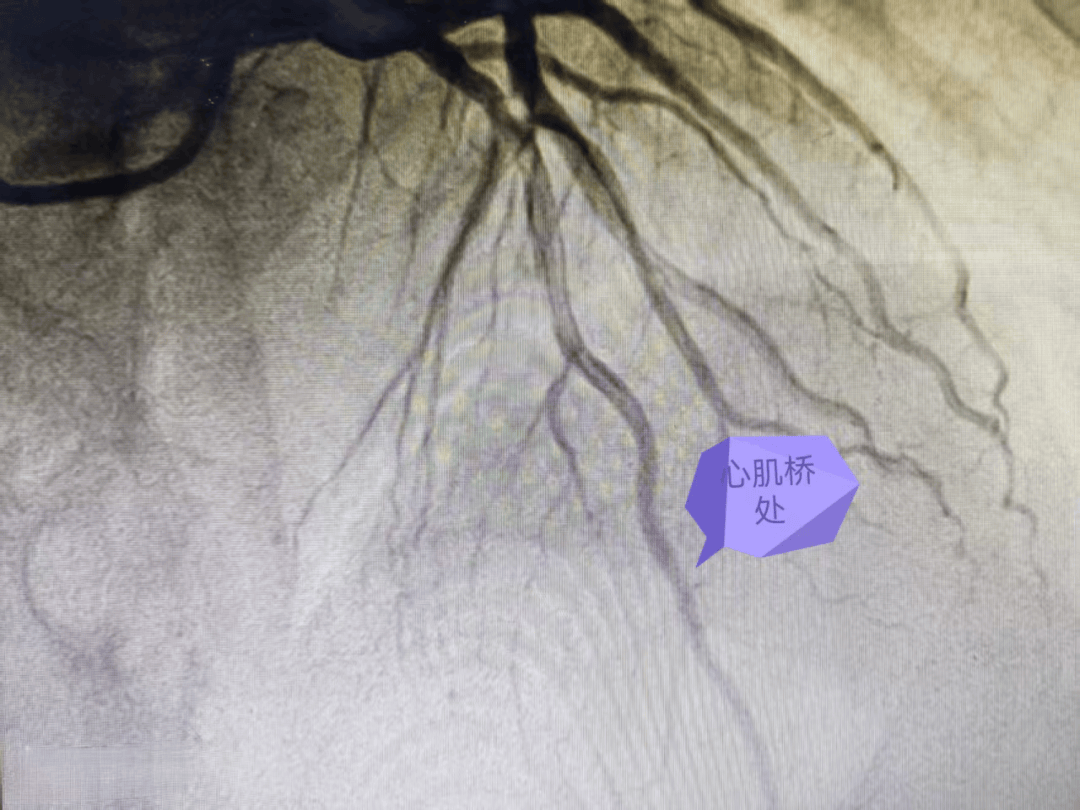

前降支心肌桥疑致急性心肌梗死一例

心肌桥

心肌桥,或称心肌桥冠状动脉,是一种较为常见的先天性冠状动脉畸形